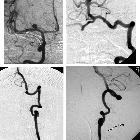

Chronic

fusiform extracranial vertebral artery aneurysm with recurrent posterior circulation emboli: Case report and review of the literature: A: Digital subtraction angiography (DSA)(anterior-posterior view) confirmed a chronic fusiform aneurysmal right vertebral artery with areas of saccular dilatation (grey arrow). The distal V3 segment of the vertebral artery (white arrow) and intra-cranial basilar artery were normal (black arrow). B: DSA (lateral view) endovascular embolization was performed with distal micro-vascular plug and platinum coils (white arrow). Contrast stagnation can be seen in the areas of saccular dilatation. C: Proximal cervical vertebral artery embolization was performed with a single micro-vascular plug (black arrow). D: Pre-embolization angiogram with injection in the left vertebral artery demonstrates normal appearances with no opacification of the right posterior inferior cerebellar artery territory (PICA). E: Post-embolization retrograde flow of contrast from the left vertebral artery fills the intra-dural right vertebral artery (white arrow) and perfuses the right PICA (black arrow).